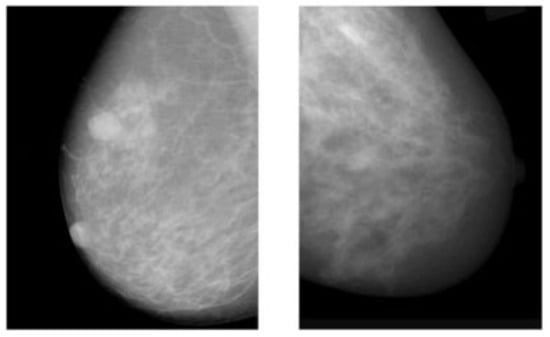

2.1. Mammograms (MMs)

The advantages of mammograms, such as being cost-effective to detect tumors in the initial stage before development, mean that MMs are the most promising imaging screening technique in clinical practice. MMs are generally images of breasts produced by low-intensity X-rays (Figure 1) [33]. In this imaging modality, cancerous regions are brighter and more clear than other parts of breast tissue, helping to detect small variations in the composition of the tissues; therefore, it is used for the diagnosis and analysis of breast cancer [34,35] (Figure 1). Although MMs are the standard approach for breast cancer analysis, it is an inappropriate imaging modality for women with dense breasts [36], since the performance of MMs highly depends on specific tumor morphological characteristics [36,37]. To deal with this problem, using automated whole breast ultrasound (AWBU) or other methods are suggested with MMs to produce a more detailed image of breast tissues [38].

For various tasks in breast cancer analysis, such as breast lesion detection and classification, MMs are generally divided into two forms: screen film mammograms (SFM) and digital mammograms (DMM). DMM is widely categorized into three categories consisting of full-field digital mammograms (FFDM), digital breast tomosynthesis (DBT), and contrast-enhanced digital mammograms (CEDM) [39,40,41,42,43,44]. SFM was the standard imaging method in MMs because of its high sensitivity (100%) in the analysis and detection of lesions in breasts composed primarily of fatty tissue [45]. However, it has many drawbacks, including the following: (1) SFM imaging needs to be repeated with a higher radiation dose because some parts of the image in SFM have lesser contrast and cannot be further improved, and (2) various regions of the breast image are represented according to the characteristic response of the SFM [19,45]. Since 2010, DMM has replaced film as the primary screening modality. The main advantages of digital imaging over file systems are the higher contrast resolution and the ability to enlarge the image or change the contrast and brightness. These advantages help radiologists to detect subtle abnormalities, particularly in a background of dense breast tissue, more easily. Most studies comparing digital and film mammography performance have found little difference in cancer detection rates [46]. Digital mammography increases the chance of detecting invasive cancer in premenopausal and perimenopausal women and women with dense breasts. However, it increases false-positive findings as well [46]. Randomized mammographic trials/randomized controlled trials (RMT/RCT) represent the most important usage of MMs, through which large-scale screening for breast cancer analysis is performed. Despite the great capability of MMs for early-stage cancer detection, it is difficult to use MMs alone for detection. Because it requires additional screening tests along with mammographic trials/RMT such as breast self-examination (BSE) and clinical breast examination (CBE), which are more feasible methods to detect breast cancer at early stages to improve breast cancer survival [38,47,48]. Additionally, BSE and CBE avoid tremendous harm due to MMs screening, such as repeating the imaging process. More details about the advantages and disadvantages of MMs are provided in Table 1.